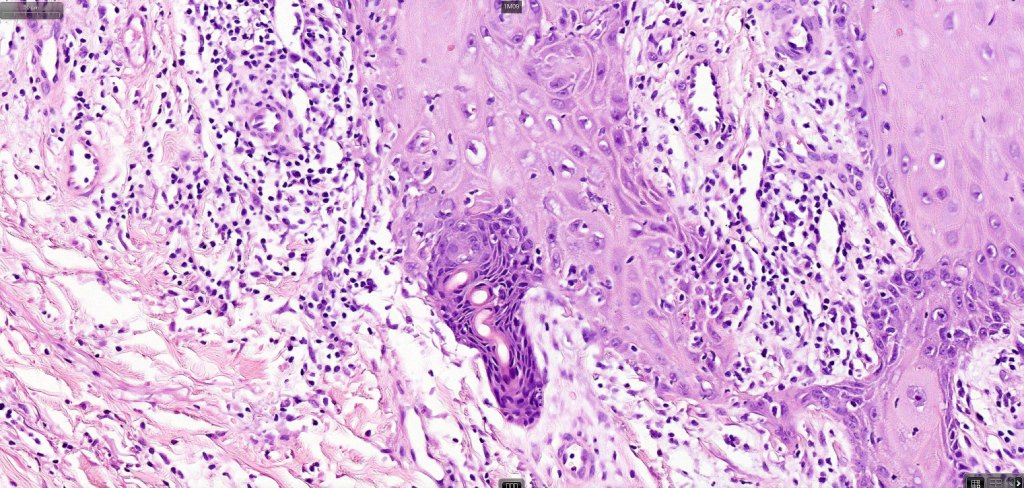

•With evolution, the epithelium flattens with underlying fibrosis and chronic inflammation including a foreign body giant cell reaction to keratin

Below is a fascinating case shared on McKee Derm by Dr. James Simpson. There is an obvious keratoacanthoma but at the edge of the lesion there is marked atypia with nuclear enlargement and pleomorphism. This is also evident in the adjacent epidermis and in the deeper nests.